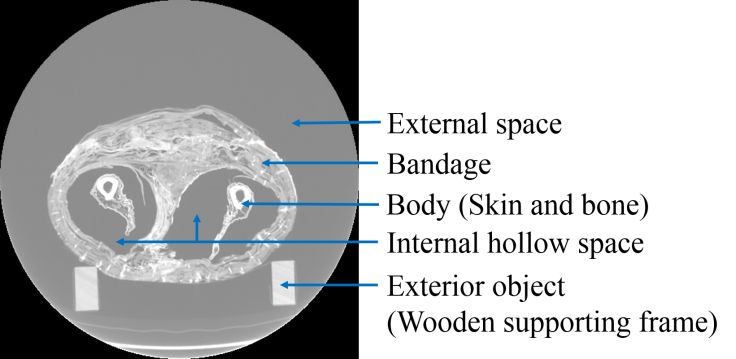

Figure 3: Visualization of axial frames of a mummy [6] selected in proximity of the thigh. (a) Some of the regions we are interested to segment are indicated. (b) Artifacts caused by presence of metals.

In Fig. 3a, we show one axial slice of a male mummy with indication of the regions to be segmented. Fig. 3b illustrates that metals present inside a bandaged mummy generate severe artifacts, which are not present in standard biomedical data.